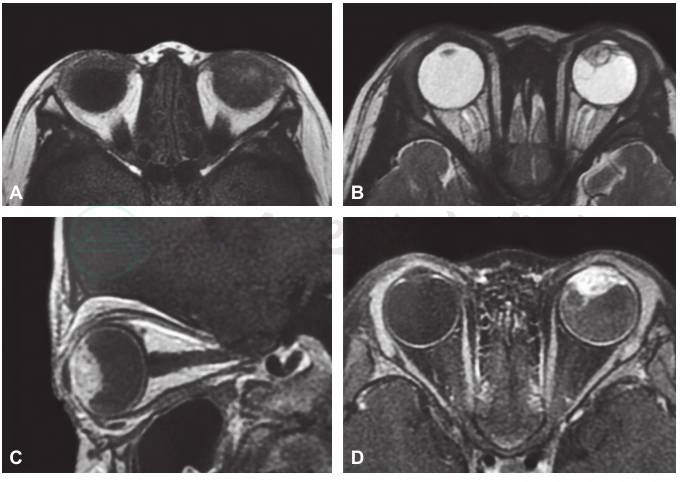

图1 眼眶CT扫描影像结果

A.水平位,B.冠状位,显示左眼内肿物位于眼球前部,肿物内可见高密度钙化影。

患儿男性,2.5岁,因发现左眼球内占位1个月就诊于首都医科大学附属北京同仁医院眼肿瘤科。患儿父母主述患儿1个月前玩耍时不慎碰伤左眼,就诊于当地医院,诊断为左眼前房积血,行眼部B型超声和眼眶CT检查后发现左眼球内占位性病变,提示视网膜母细胞瘤可能性大,故建议转诊首都医科大学附属北京同仁医院诊治。患儿既往身体健康,足月顺产,否认吸氧史及其他病史,否认家族遗传病史。患儿全身一般情况良好。眼部检查:双眼视力检查不合作,右眼眼压Tn,左眼T-1,左眼混合充血,角膜水肿、混浊,前房积血,眼内窥不清,左眼外斜视15△,眼球运动正常。右眼检查未见明显异常。本院眼部医学影像学检查结果:B型超声检查显示左眼眼轴较右侧缩短,左眼球内实性占位病变,不能排除视网膜母细胞瘤。CT扫描显示左侧眼球内高密度影并可疑性软组织影,外伤后出血机化可能性大,不能排除恶性病变可能(图1)。MRI扫描显示左侧眼球晶状体-虹膜-睫状体区占位性病变的可能性大,外伤后出血机化,形成增生性组织,恶性肿瘤待排除(图2)。血常规、尿常规及生化指标的实验室检查均未发现异常。

该病例的特点有:患儿2.5岁,年龄小;有外伤史;左眼混合充血,角膜水肿混浊、前房积血、左眼外斜视;B超示左眼球内实性占位,左眼轴较右眼短,提示左眼已经发生眼球萎缩,说明病史较长,病情较重;CT示左眼球内实性占位,可见钙化斑,如果没有外伤史,此种改变基本可以诊断为视网膜母细胞瘤;MRI示左眼病变累及部位为晶状体-虹膜-睫状体区域,而此区域却不是视网膜母细胞瘤发生的常见区域。

大多数视网膜母细胞瘤患者的最大特点包括发病年龄小、眼球内实性占位、CT扫描可见眼球内钙化斑出现。如果髓上皮瘤发生在眼内,眼眶CT和MRI扫描可见眼球内实性占位性病变,且CT扫描还显示眼球内有钙化斑点,此时极易误诊为视网膜母细胞瘤。本例髓上皮瘤患儿CT扫描结果显示眼内出现具有钙化斑样实性占位,且患儿年龄2.5岁,故初诊时高度怀疑为视网膜母细胞瘤,后经病理组织学检查证实为畸胎瘤样髓上皮瘤,才得以确诊。